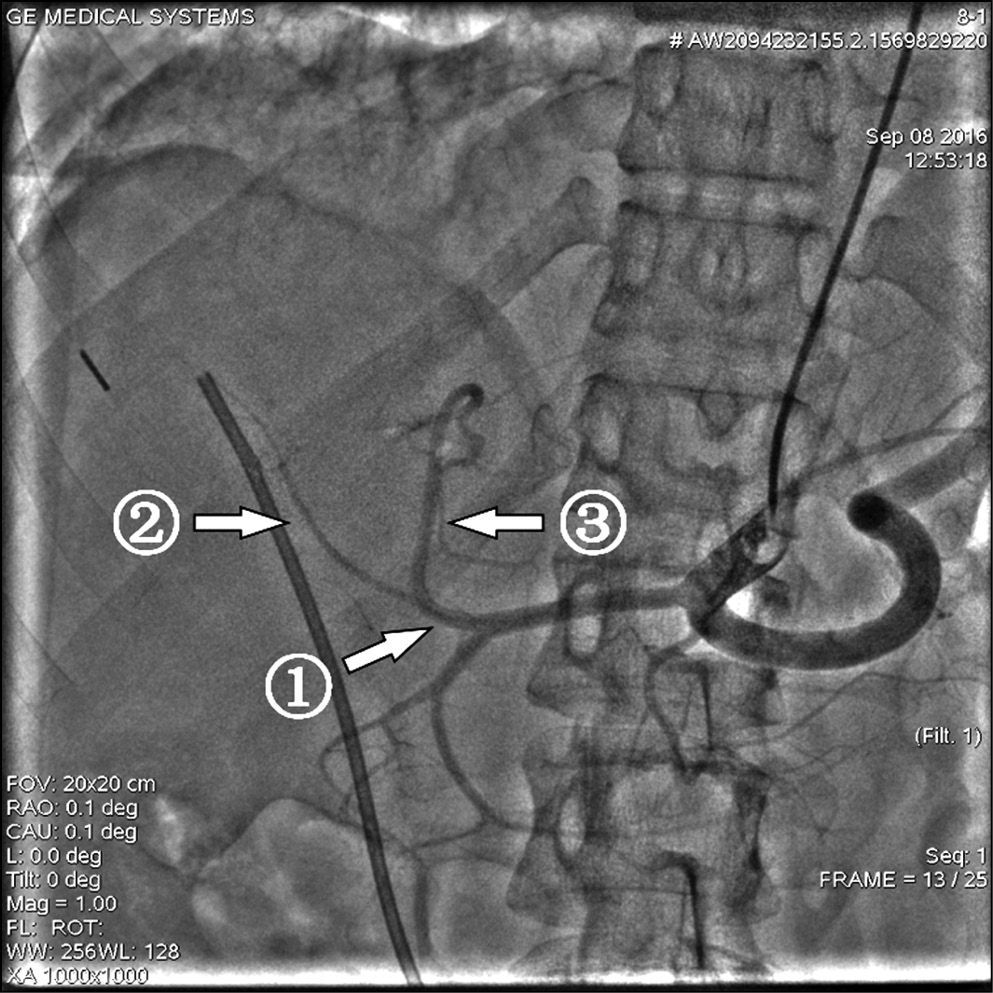

Однако при планировании химиоэмболизации артерий печени необходимо учитывать не только различные варианты кровоснабжения печени, но и особенности пробега висцеральных артерий. Так, у одного пациента была обнаружена повышенная извитость печеночных артерий, что исключало бы проведение ХЭПА в монолобарном варианте (рис. 3).

Рис. 3. Вариант кровоснабжения печени, выраженная извитость печеночных артерий

Примечание. 1 — общая печеночная артерия, 2 — правая печеночная артерия, 3 — левая печеночная артерия.

Микрокатетерная техника катетеризации позволила выполнить первоначальный план доступа в дистальное сосудистое русло (рис. 4).

Рис. 4. Селективная катетеризация сегментарных ветвей левой печеночной артерии при выраженной извитости печеночных артерий

Примечание. 1 — ангиографический катетер 5F в устье чревного ствола, 2 — микрокатетер, проходящий из чревного ствола в левую печеночную артерию, 3 — сегментарные ветви левой печеночной артерии.